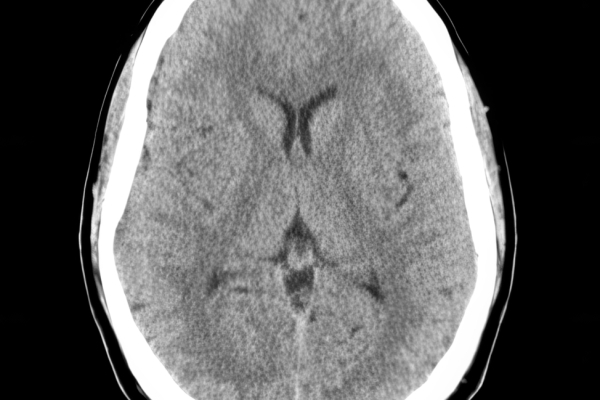

CT Untersuchung Bild

Die MRT (Magnetresonanztomographie) arbeitet mit Magnetfeldern und Radiowellen und eignet sich besonders für Untersuchungen der Weichteile wie Gehirn, Muskeln oder Gelenke. Die CT (Computertomographie) nutzt Röntgenstrahlen und liefert schnelle, hochauflösende Bilder, insbesondere für Knochen, Lunge oder innere Organe. Die Wahl der jeweiligen Untersuchung richtet sich an das individuelle Krankheitsbild und wird bei der Überweisung festgelegt.